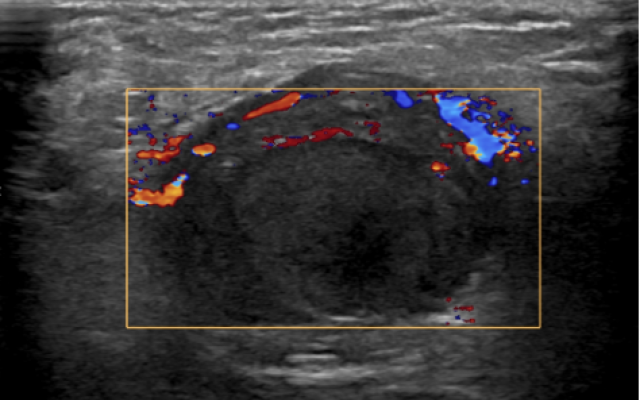

Een 9-jarige jongen kwam op de afdeling Spoedeisende Hulp vanwege een pijnlijke zwelling in de rechter lies. Hij had de dag tevoren pijn gekregen rechts in de onderbuik, waarbij hij de zwelling had opgemerkt. De pijn verdween met pijnstillers na een bezoek aan de huisarts. ’s Nachts nam de pijn weer toe en gaf patiënt veel over. De huisarts stuurde hem door. Wij vonden een pijnlijke zwelling in de rechter lies, met daarnaast een leeg scrotum aan de rechter zijde. Op patiënts zogenaamde ‘ballenkaart’ was in het verleden wel indaling van de testis gedocumenteerd. Bij echografie werd een getordeerde…